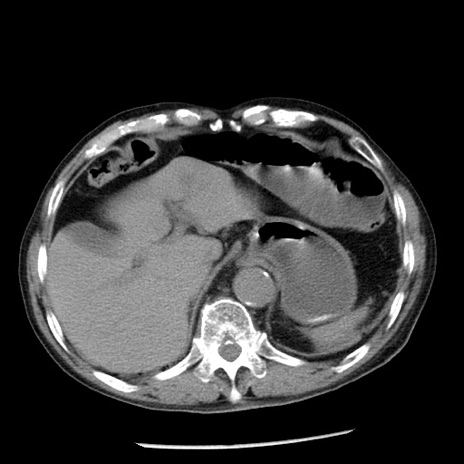

症例26(横断像)

【症例】80歳代男性

【主訴】嘔吐

【現病歴】昨晩2回嘔吐あり、今朝になっても嘔吐あり。来院。

【既往歴】胃潰瘍

【身体所見】意識清明、BT 37.6℃、BP 166/95mmHg、HR 100bpm、SpO2 97%、腹部:平坦・軟、腸蠕動音聴取良好、圧痛なし。

【データ】WBC 21900、CRP 1.46